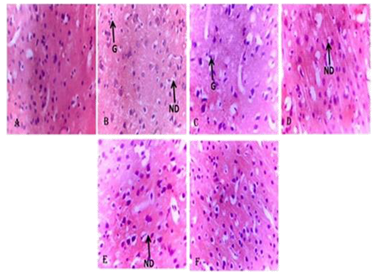

Photomicrograph of the Cortical Sections of the Brain Showing the effect of PMCV002 after Scopolamineinduced Amnesia in Mice. (a). Distilled water group showing normal cortex (b). Scopolamine 1 mg/kg group showing severe gliosis and neuronal degeneration (c). Donepezil 5 mg/kg showing mild gliosis (G) (d). PMCV 002 at 1000 mg/kg showing mild neuronal degeneration (ND) (e). PMCV002 at 500 mg/kg showing mild neuronal degeneration (ND) (f). PMCV 002 at 250 mg/kg showing normal features.

Fig. 1. Photomicrograph of the Cortical Sections of the Brain Showing the effect of PMCV002 after Scopolamine-induced Amnesia in Mice. (a). Distilled water group showing normal cortex (b). Scopolamine 1 mg/kg group showing severe gliosis and neuronal degeneration (c). Donepezil 5 mg/kg showing mild gliosis (G) (d). PMCV 002 at 1000 mg/kg showing mild neuronal degeneration (ND) (e). PMCV002 at 500 mg/kg showing mild neuronal degeneration (ND) (f). PMCV 002 at 250 mg/kg showing normal features. Image Credit: Image courtesy of Adedapo Adesokan et al., in partnership with ELRIG (UK) Ltd.